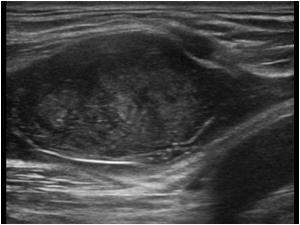

Периферическая шваннома

В серошкальном режиме визуализируется овальное гипоэхогенное или неоднородное образование вдоль хода периферического нерва с чёткими границами, смещающее или деформирующее нерв.

В режиме мягкотканевого сканирования определяется изменение толщины нерва выше и ниже опухоли, структура капсулы опухоли и наличие анэхогенных или гипоэхогенных зон внутри.

В допплеровском режиме фиксируется усиление кровотока в сосудистой сети по периферии опухоли или внутри неё.